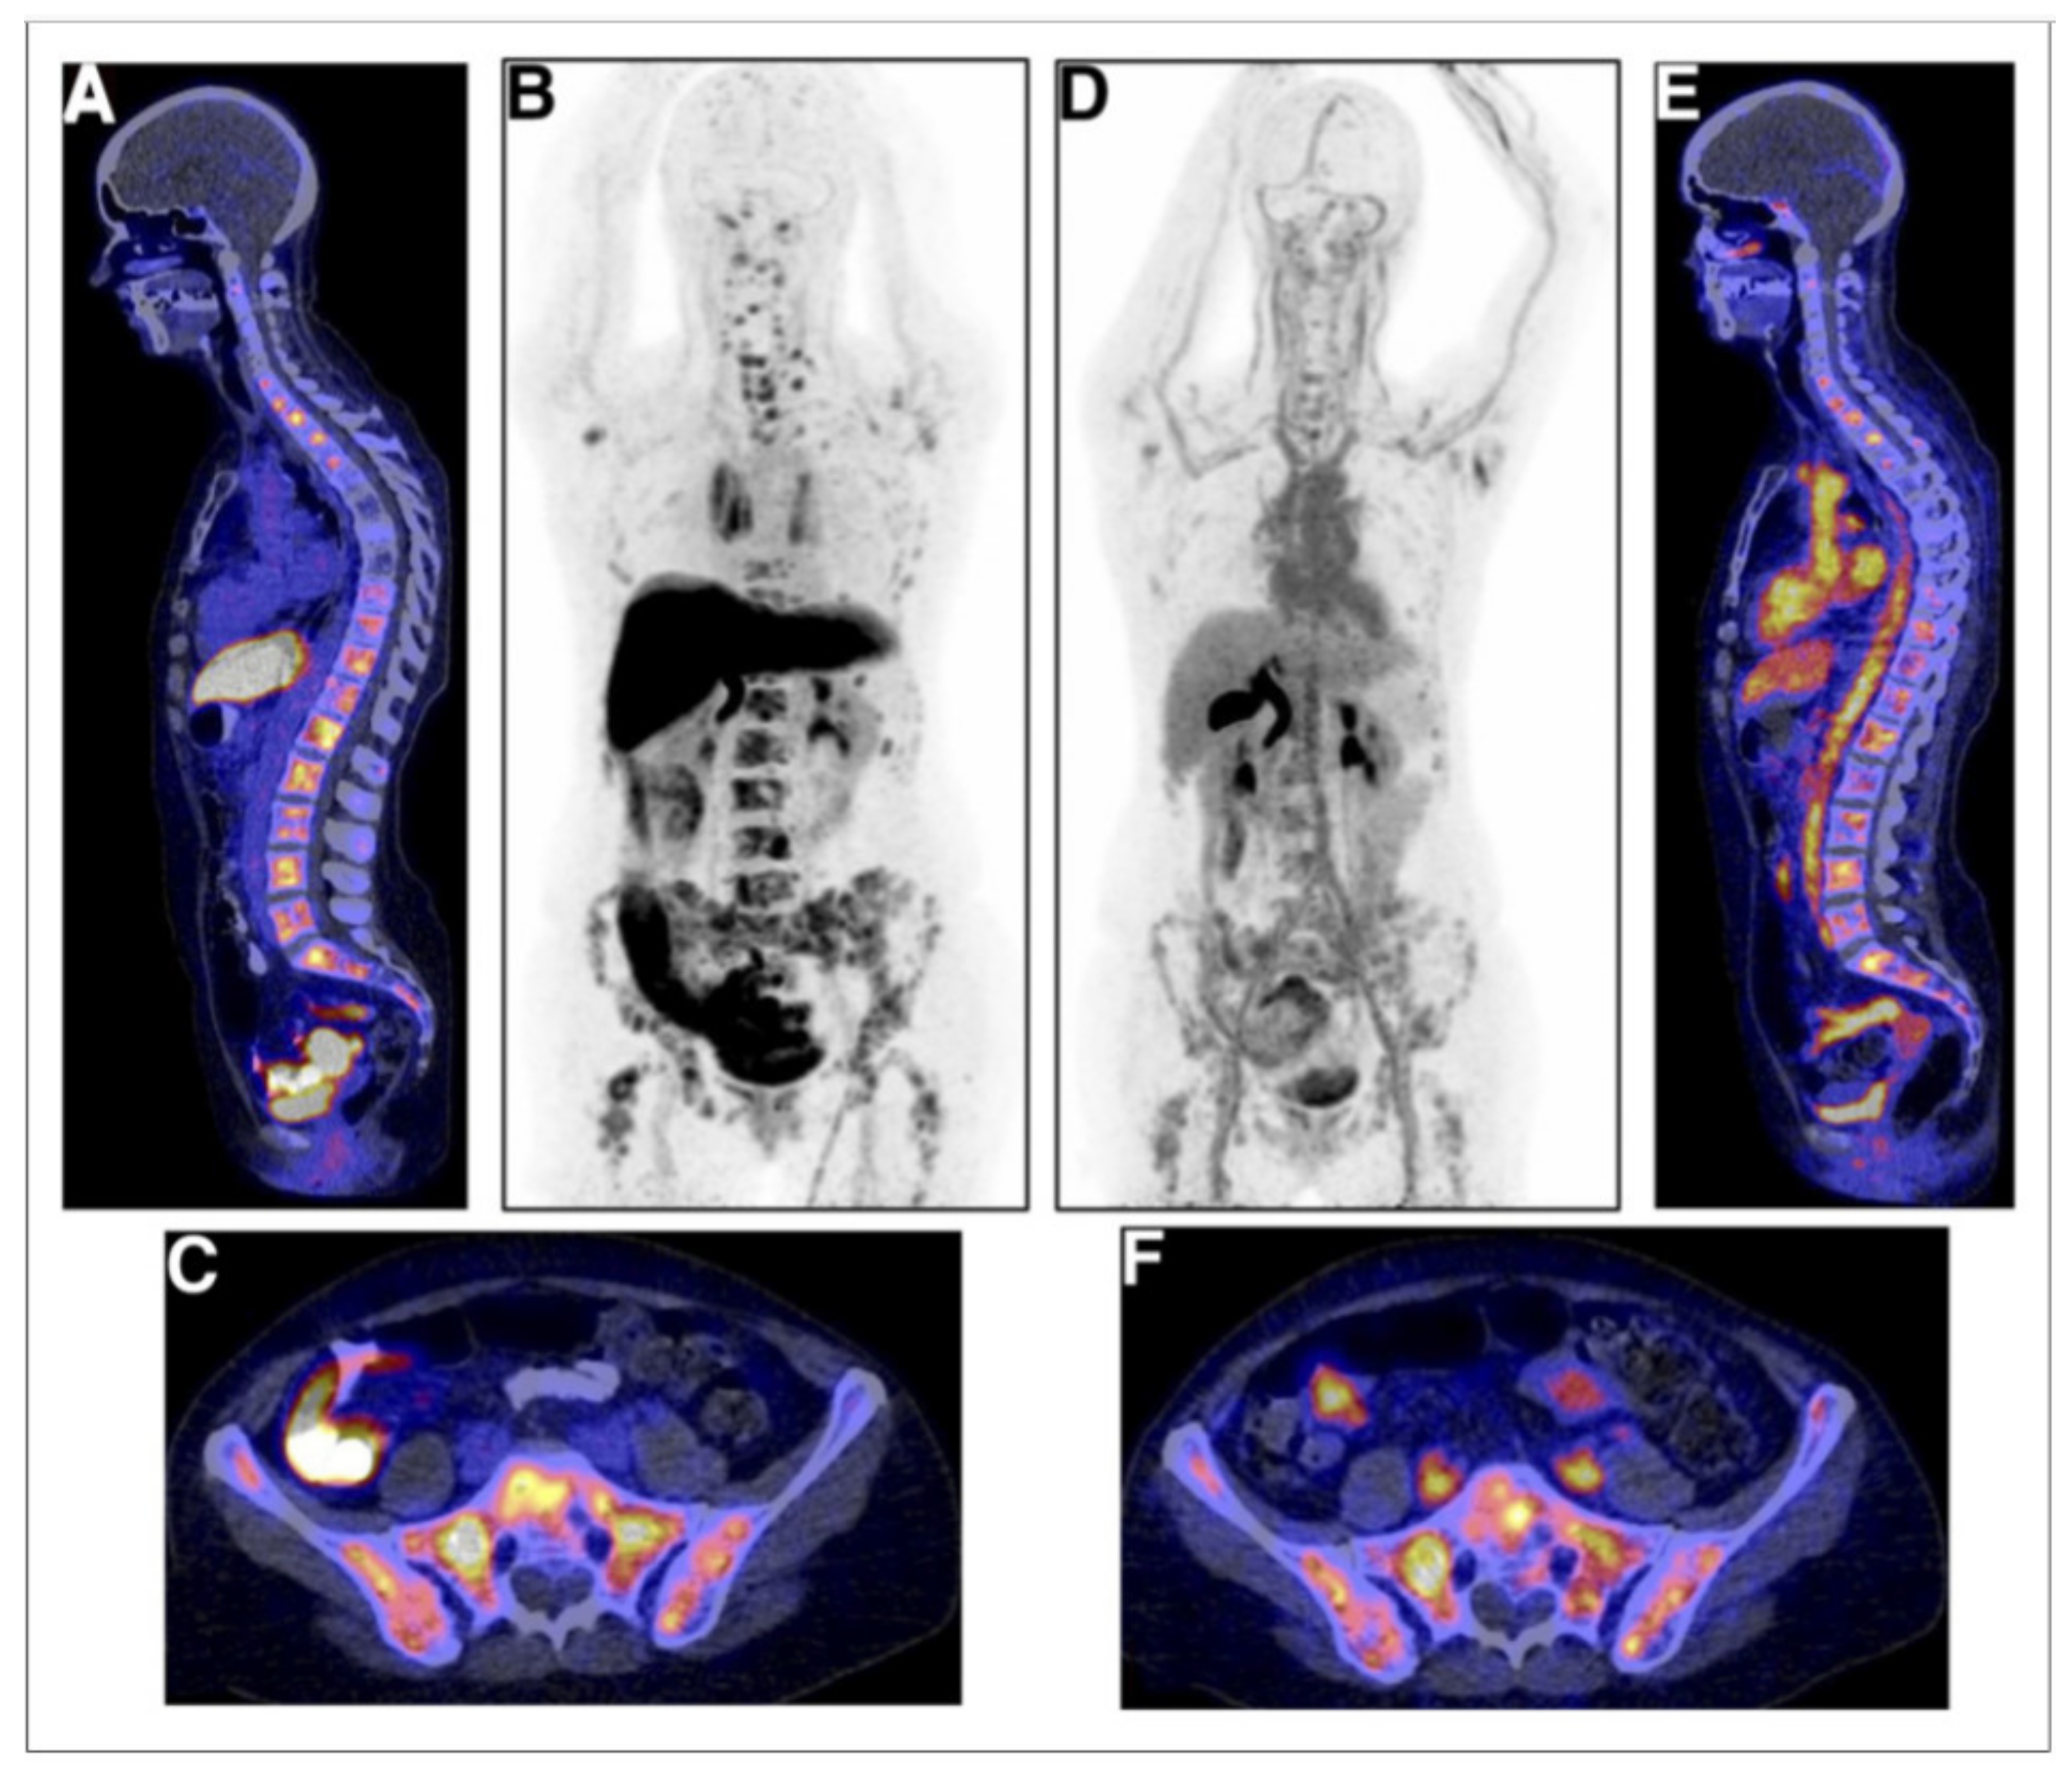

- Fox, J.J.; Gavane, S.C.; Blanc-Autran, E.; Nehmeh, S.; Gönen, M.; Beattie, B.; Vargas, H.A.; Schöder, H.; Humm, J.L.; Fine, S.W.; et al. Positron Emission Tomography/Computed Tomography-Based Assessments of Androgen Receptor Expression and Glycolytic Activity as a Prognostic Biomarker for Metastatic Castration-Resistant Prostate Cancer. JAMA Oncol. 2018, 4, 217–224. [Google Scholar] [CrossRef]

| Vargas 2014 [30] | 38 | To determine associations between [18F]FDHT PET/CT and overall survival | Patients with higher SUVmax on [18F]FDHT PET/CT had significantly shorter overall survival | ||

| Fox 2018 [34] | 133 | To determine combined value of [18F]FDG and [18F]FDHT as prognosticator | [18F]FDHT [18F]FDG | Bone 5.5, lymph nodes 6.4, prostate 7.6 | Three phenotypes were AR1Glyc1, AR1Glyc0, and AR0Glyc1 were identified. If AR is negative and FDG positive, it has a negative impact on survival |